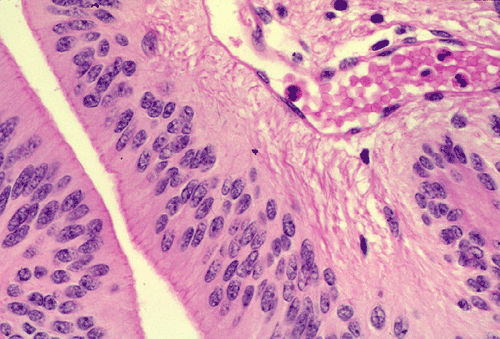

The histopathology of the tumor is fairly similar in different parts of the of the tumor and the papillary structures are the obvious (Panel A). On medium and high magnification (Panel B and C respectively), the cores of the papillary structure is composed of thin walled blood vessels. The tumor cells appear to appear in a pattern reminiscent of the pseudocolumnar arrangement of the respiratory respiratory epithelium except that no basement membrane can be identified. The cores are also not composed of collagenous tissue but by fibrillary process that appear to extends from the nuclei. A zone of hyponuclear area is present between the nuclei and the vascular channels (delimited by arrows in Panel C). No cilia are noted on the surface epithelium and no mucin production is noted. The cytoplasmic border is very indistinct. The nuclei appear to be rather bland appearing and mitotic figures are not readily seen. There is neither endothelial proliferation nor necrosis.

Papillary ependymoma, as illustrated in this case, is a rare variant. These tumors typically appear as papillary fronds covered by multilayered ependymal tumor cells. The most superficial layer may have epithelium-like surfaces similar to those of ependymal rosettes. These tumors must be distinguished from metastatic papillary carcinomas and choroids plexus tumors. One salient feature is that papillary ependymomas have no basement membrane. The superficial epithelial tumor cells merge imperceptibly with the underneath tumor cells. Papillary ependymoma can express cytokeratin. It is not rare to see focal papillary formation in an otherwise classic ependymoma. However, tumors composed predominantly of papillary structure as illustrated in this case is uncommon.